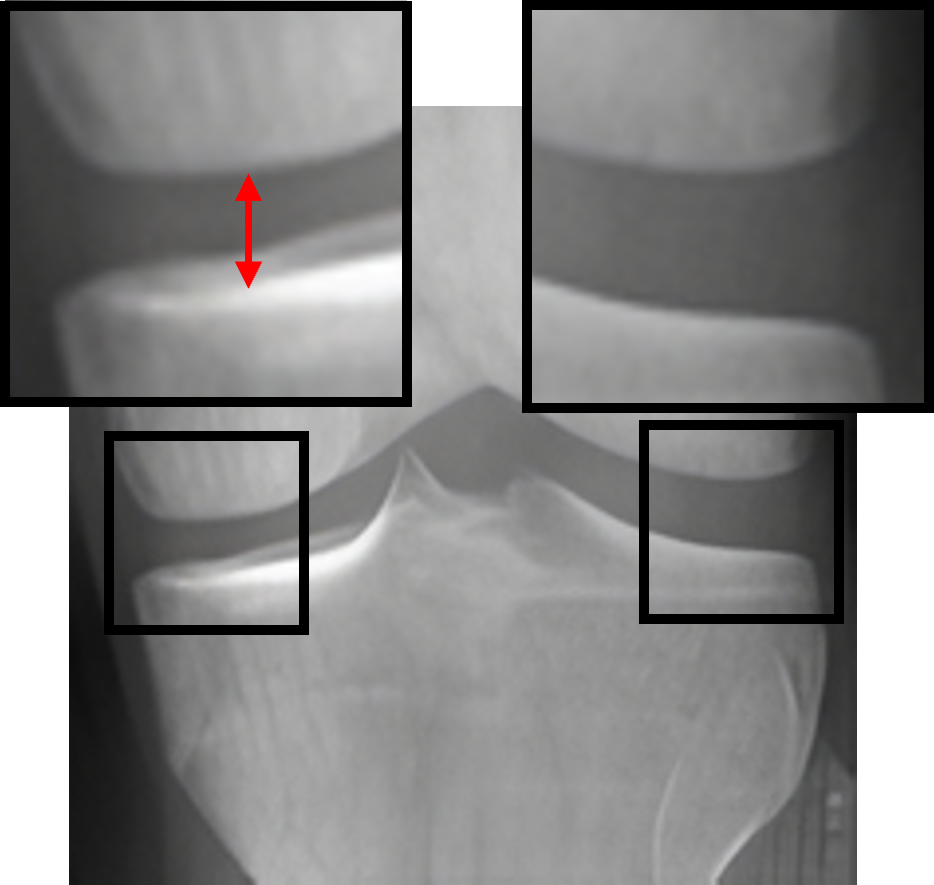

Table 2: Visualization of the synthesized intermediate frames

Input image Synthesized intermediate framessuperscriptSynthesized intermediate frames\stackrel{{\scriptstyle\text{Synthesized intermediate frames}}}{{\makebox[284.52756pt]{\rightarrowfill}}} Input image

xSsubscript𝑥𝑆x_{S} xS(φη=0.25)subscript𝑥𝑆subscript𝜑𝜂0.25x_{S}(\varphi_{\eta=0.25}) xS(φη=0.5)subscript𝑥𝑆subscript𝜑𝜂0.5x_{S}(\varphi_{\eta=0.5}) xS(φη=0.75)subscript𝑥𝑆subscript𝜑𝜂0.75x_{S}(\varphi_{\eta=0.75}) xTsubscript𝑥𝑇x_{T}

KL-0 KL-1∗∗ KL-2∗∗ KL-3∗∗ KL-4

[Uncaptioned image] [Uncaptioned image] [Uncaptioned image] [Uncaptioned image] [Uncaptioned image]

• *

The morphed areas of each frame were highlighted within black boxes, the red arrow and red circle indicate the locations of JSN and osteophyte formation, respectively. A shorter arrow indicates a smaller joint space (i.e., a narrower distance between the tibia and femur), while a larger circle indicates more osteophytes.

• **

The expected labels.

4.2 Visualization of the synthesized intermediate frames

In Table 2, we show the source image xSsubscript𝑥𝑆x_{S}, the target image xTsubscript𝑥𝑇x_{T}, and their intermediate frames (i.e., xS(φη=0.25)subscript𝑥𝑆subscript𝜑𝜂0.25x_{S}(\varphi_{\eta=0.25}), xS(φη=0.5)subscript𝑥𝑆subscript𝜑𝜂0.5x_{S}(\varphi_{\eta=0.5}) and xS(φη=0.75)subscript𝑥𝑆subscript𝜑𝜂0.75x_{S}(\varphi_{\eta=0.75})), which is crucial in understanding how the source images evolve into their registered state. The progressive alignment is quantified by the parameter η𝜂\eta evenly divided into 0.25, 0.5, and 0.75, which represents the extent of transformation at each stage of KOA, corresponding to KL-1, KL-2, and KL-3, respectively. As can be seen, xS(φη=0.25)subscript𝑥𝑆subscript𝜑𝜂0.25x_{S}(\varphi_{\eta=0.25}) shows the initial stage of the morphing process where the morphs are minimal and closely resemble the source image. For xS(φη=0.5)subscript𝑥𝑆subscript𝜑𝜂0.5x_{S}(\varphi_{\eta=0.5}), the morph is more pronounced, introducing clear signs of osteophytes and beginning to show a narrowing of the joint space. It is noteworthy that this frame is critical as it represents the halfway anchor point of the KOA temporal evolution process, showing a balanced mix of characteristics from both the source and target images. xS(φη=0.75)subscript𝑥𝑆subscript𝜑𝜂0.75x_{S}(\varphi_{\eta=0.75}) signifies an advanced stage of morph, introducing moderate multiple osteophytes, definite narrowing of the joint space, some sclerosis, and possible deformity of bone contour.